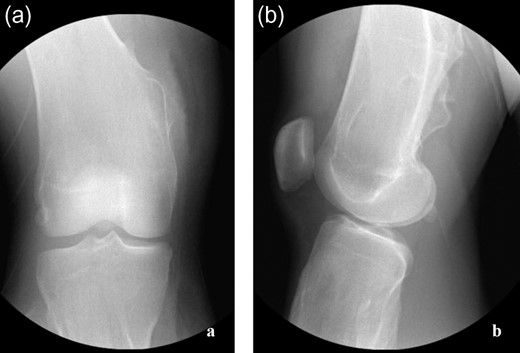

The procedure began with examination under anesthesia—the right leg could be forcefully extended but resulted in significant tension about the posteromedial soft tissues of the leg. The limb was circumferentially prepped and draped in the standard orthopedic fashion without the use of a tourniquet. The osteochondromas were localized (Fig. 2a–c) and exploration revealed a bursa superficial to the osteochondroma. The gracilis tendon was in its appropriate anatomic position cranial to the pedunculated osteochondroma. The semitendinosus tendon was incarcerated inferior to the osteochondroma (Fig. 3a), creating the locked knee effect. The hooked tendon was protected, and the 3 cm osteochondroma (Fig. 3b) was removed with an oscillating saw, freeing the entrapped tendon and restoring normal movement of her knee. Radiographic imaging (Fig. 4a and b) confirmed satisfactory removal of the lesions, and the wounds were closed. At the 3-month follow-up, the patient had returned to all desired activities with no recurrent medial knee pain or locking.

(a–c) Initial intraoperative radiographic images obtained to locate the lesions.